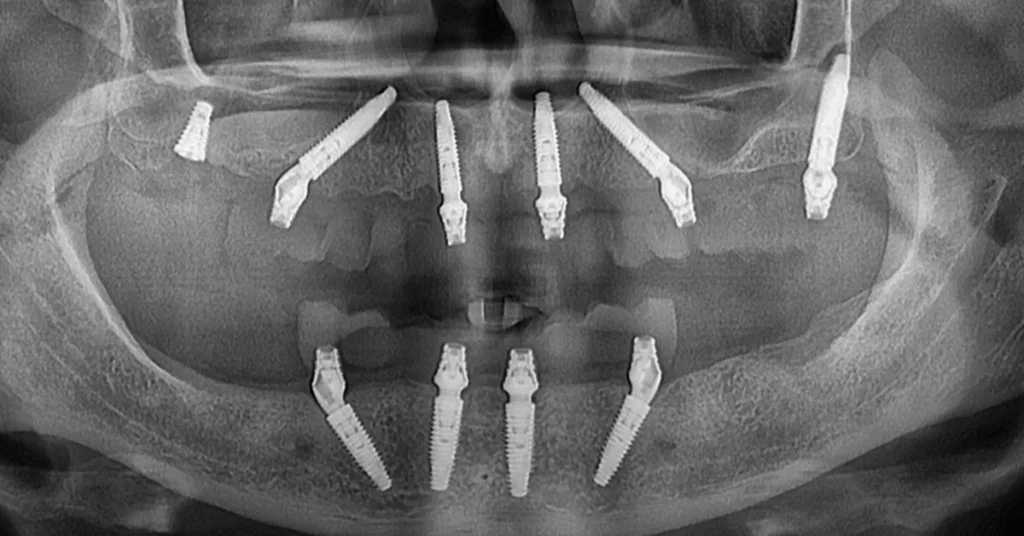

Pacientul s-a prezentat cu carii extinse, cativa dinti ramasi si resturi radiculare. Tratamentul a constat in inserarea a 6 implanturi la maxilar (4 implanturi standard si 2 implanturi pterigoide) si 4 implanturi standard la mandibula. Dupa interventie, pacientul a purtat o lucrare provizorie fixa timp de 6 luni, permitand osteointegrarea completa. La final, s-au realizat lucrarile definitive din ceramica stratificata pe zirconiu, atat la maxilar, cat si la mandibula, obtinand un rezultat estetic si functional optim.